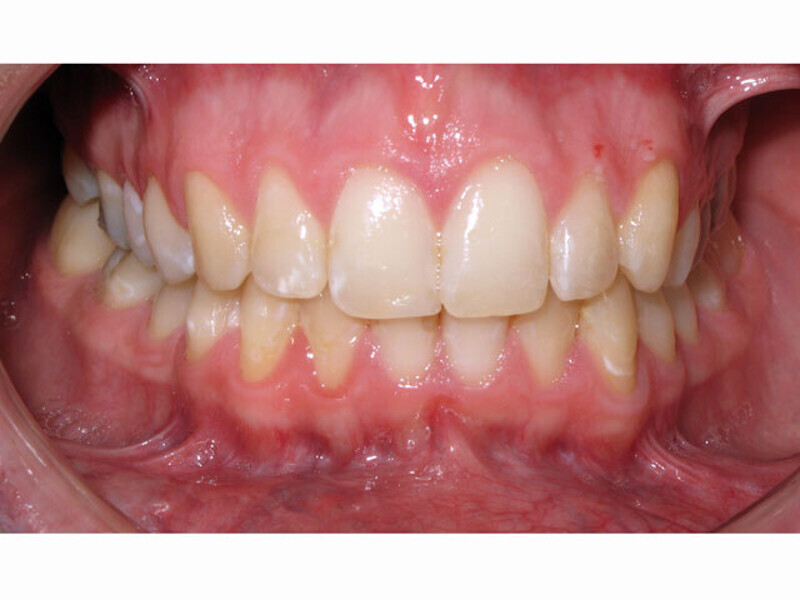

ClearCorrect treatment of crowding